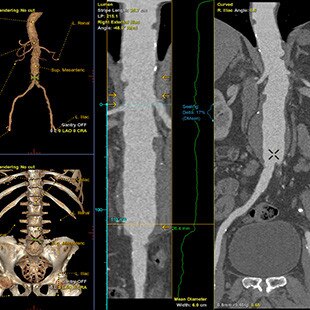

Procédures complexes de réparation endovasculaire des anévrismes abdominaux (EVAR)

- La solution EVAR ASSIST 2 inclut FlightPlan for EVAR CT et EVARVision, et requiert la station de travail AW équipée de Volume Viewer, Volume Viewer Innova, VessellQ Xpress et Autobone Xpress. Ces applications sont vendues séparément.